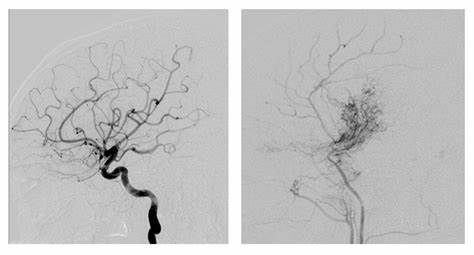

为了补偿狭窄的动脉,大脑会创建侧支血管,以试图将富含氧气的血液输送到大脑的贫困区域。当在血管造影照片上看到时,这些微小的侧支血管具有朦胧的薄膜状外观。日本人是一个描述这种状况的人,他们将其命名为“烟雾病”。比起正常血管更脆弱的是,这种薄薄的附子可能破裂并渗入大脑,导致出血。烟雾病通常会影响大脑的两侧,并常伴有动脉瘤。

烟雾病的进展遵循典型过程,可根据血管造影结果分为不同阶段。

一阶段:颈内动脉狭窄

二阶段:大脑底部的烟雾纹血管的发育

三阶段:烟雾病血管加剧和颈内动脉狭窄(在此阶段诊断出的大多数病例)

四阶段:较小化烟雾弥漫性血管和头皮增加的侧支血管

五阶段:减少烟雾烟雾和明显的颈内动脉狭窄

六阶段:烟雾病血管消失,颈内动脉完全阻塞以及头皮上的大量侧支血管